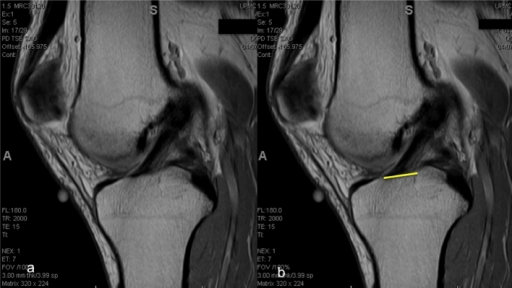

Describe the key technical principles for ACL reconstruction. Where should the tunnels be positioned?